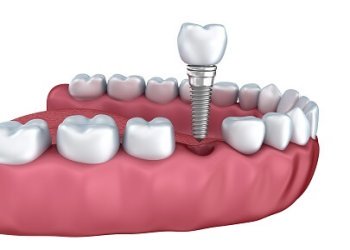

Імплантація - це метод вживлення імплантату (штучного кореня) у верхню або нижню щелепу.Такий штучний корінь виготовляється з спеціального сплаву, що надійно вживлюється в кістку та стає надійною опорою, на яку встановлюється коронка.

- Двоетапна імплантація відбувається в два послідовні етапи: спочатку здійснюється встановлення імпланту та витримується термін його повної остеоінтеграції (2-4 місяці, в залежності від щелепи), після чого встановлюється коронка;